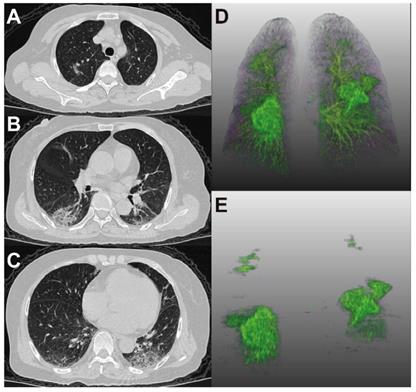

Figure 4 and 5 showed two typical cases with and without clinical endpoint during hospitalization.

Figure 4

65-year-old woman with coronavirus disease 2019. A-C. Non-contrast CT was performed on day of admission. D. Three-dimensional volume-rendered reconstruction shows the distribution of the opacities. E. Pulmonary opacities segmented by AI system. The patient had history of diabetes and hypertension and showed fever at admission. Patient developed acute respiratory failure at the third day of hospitalization. Lung CT images showed large areas of bilateral consolidation and ground-glass opacities, specifically in the upper lungs.

Theranostics Image